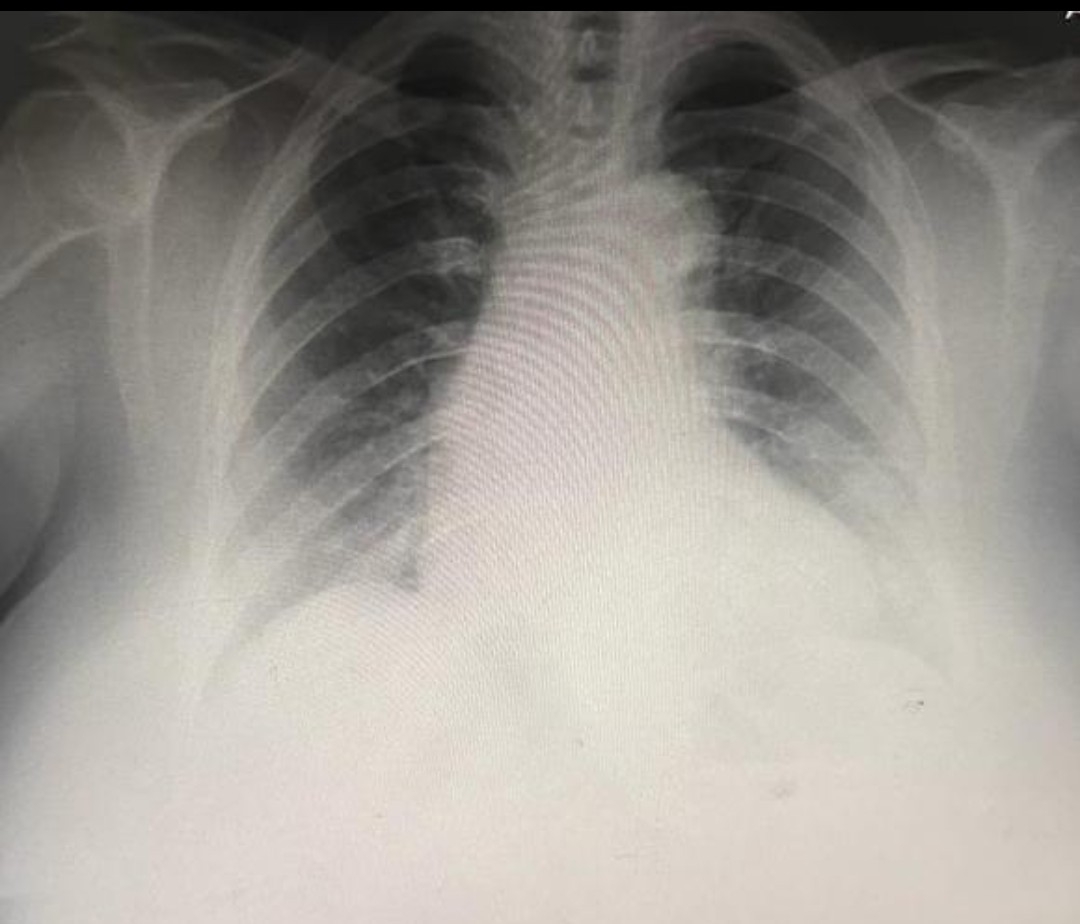

CHEST X-RAY